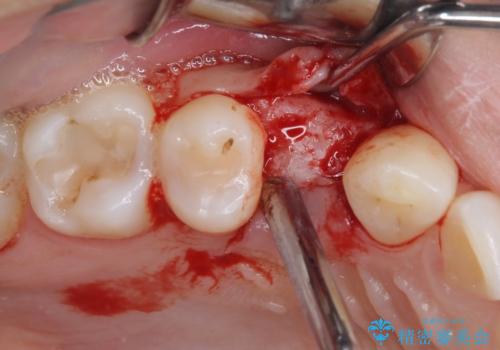

- 他院で抜歯が必要と診断され、インプラント治療を希望して来院された患者様です。

口を開けたときに目に付く領域であったので、ジルコニアカスタムアバットメントを用いたインプラント治療を行うこととしました。

インプラントは、人工骨を用いた際の骨誘導能が比較的高いとさせるストローマン社のSLActiveを使用しました。